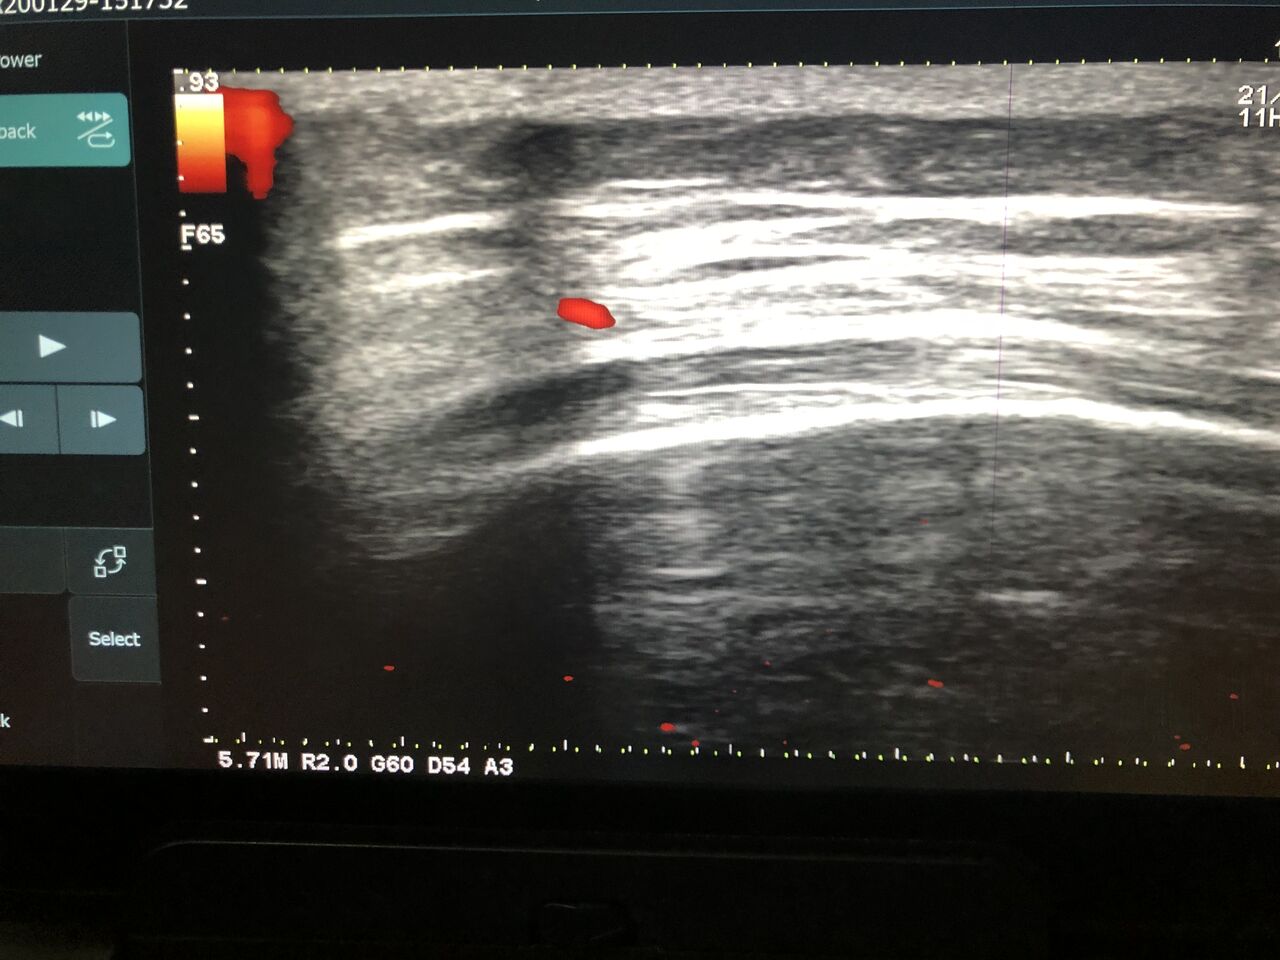

チームドクターしている

社会人野球選手 クロスプレーで受傷

骨の打撲で負傷  骨挫傷を起こし

筋肉をほぐし、テーピング、立体動態波で

早期復帰を目指す